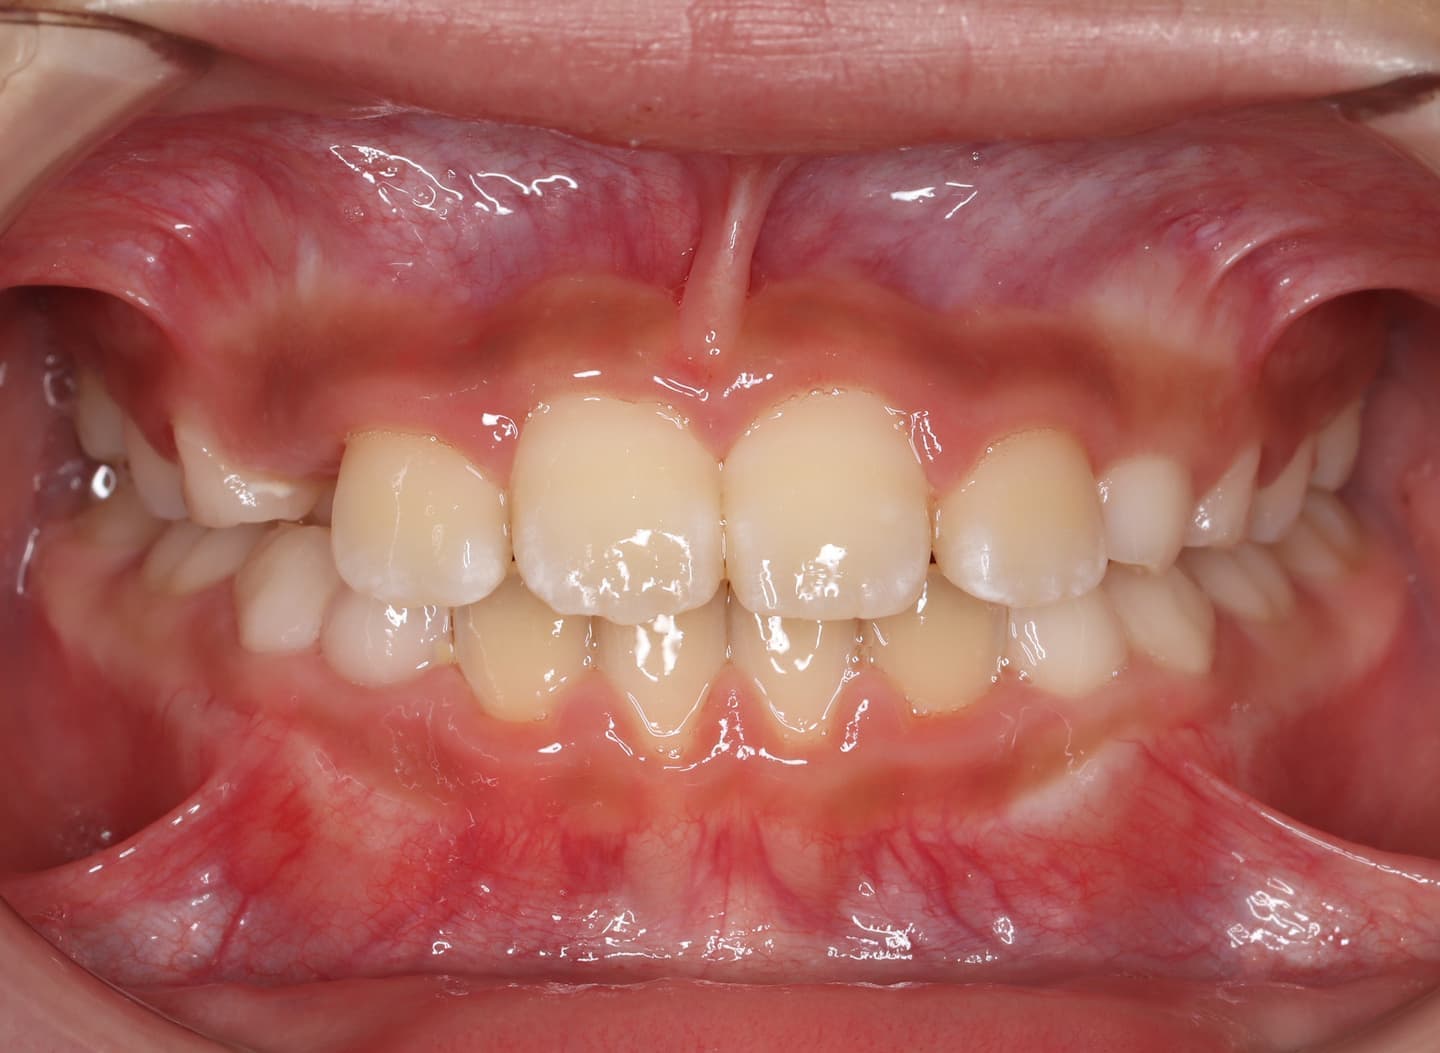

診断:初診時では右上3番の萌えるスペースがほとんどなく、顔と上顎と下顎の正中に対して、上顎前歯の正中が右にずれこんでいます。その影響で右上2番が右下乳歯Cと反対咬合になっています。放置すると、右上3番が埋伏歯になり、下顎の成長が左方向に流れるので、成長とともに顔面の非対称が増悪されることが予測されます。

治療前

右上乳犬歯が既に脱落しており、右上犬歯の萌出スペースがゼロになっています。